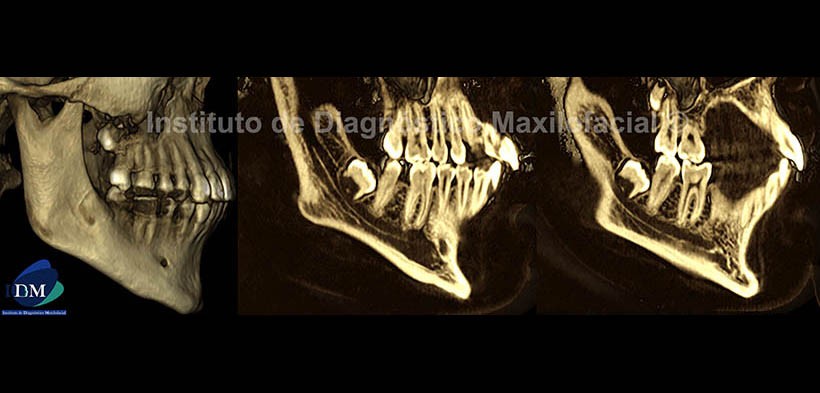

En las vistas tridimensionales se aprecian imágenes comparativas de ambos lados de la mandíbula, tanto en planos superficiales como profundos, los cuales muestran los signos descritos en los cortes anteriores. Se observa el conducto dentario inferior del lado derecho (Fig.6) junto con su conducto accesorio; y en el lado izquierdo (Fig.7), se observa el aumento del calibre del conducto dentario inferior y la mencionada alteración de la morfología del cuerpo, ángulo y rama ascendente. Nótese el severo aplanamiento del cóndilo mandibular.